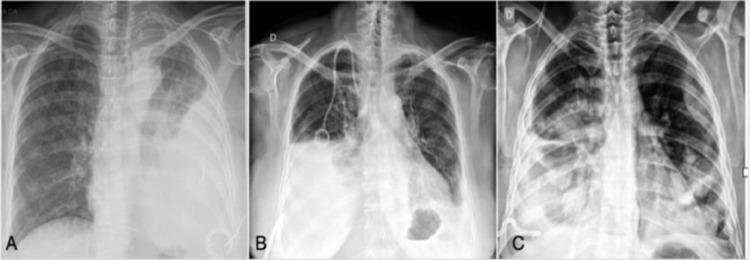

Of the 86 patients identified for inclusion in the study, 62 were women (72%). Their mean age was 56.3±12.6 years. The median pleural drainage time was 9 days, and 20 patients (23.3%) developed empyema. In the univariate analysis, both drainage time (p = 0.038) and the use of antibiotics prior to pleurodesis (p < 0.001) were risk factors for pleural empyema. Multivariate analysis also identified the use of antibiotics as an independent risk factor (Odds Ratio [OR] 9.81; 95% Confidence Interval [95% CI] 2.87‒33.54). Although the pulmonary expansion was not associated with empyema in the multivariate analysis, patients with less than 50% pulmonary expansion had a 4.5-times increased risk of empyema (95% CI 0.90‒22.86; p = 0.067), and patients with 50‒70% pulmonary expansion had a 3.8-times increased risk of empyema (95% CI 0.98‒15; p = 0.053) after pleurodesis.

The study suggests that antibiotic therapy prior to talc slurry pleurodesis may increase the risk of developing empyema. Furthermore, pleurodesis should be considered with caution in patients with long-duration chest tube placement and incomplete lung expansion.